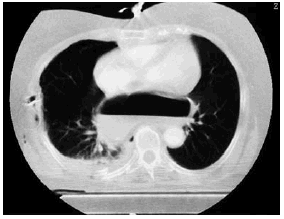

Mujer de 72 años sin antecedentes de interés, que ingresó en la Unidad de Cuidados Intensivos tras politraumatismo secundario a atropello. En los estudios radiológicos simples se objetivó fracturas de ambos fémures y de cúbito derecho, así como fracturas costales derechas junto con neumotórax y contusión pulmonar ipsilateral. Llamó la atención en la radiografía simple de tórax la presencia de una burbuja de aire a nivel centromediastínico (fig. 1). En la tomografía de tórax se observó que parte del estómago se encontraba en el tórax, retrocardíaco (fig. 2). El antro gástrico era intratorácico y aparentemente el fundus se encontraba infradiafragmático (fig. 3), lo cual fue interpretado como hernia paraesofágica postraumática. La paciente fue intervenida quirúrgicamente de urgencia; el estómago estaba contenido en un gran saco herniario con un vólvulo mesenterio axial. Había un gran orificio diafragmático. Se procedió a la reducción y devolvulación, así como a la extirpación del saco peritoneal, con funduplicatura de 360° y oclusión posterior del orificio hiatal. La paciente evolucionó favorablemente, y fue dada de alta de la UCI a los cinco días del ingreso.

Figura 2.

Figura 3.